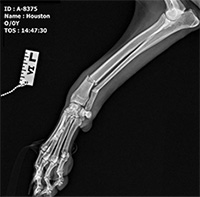

MAGSR's medical fund has been renamed in honor of a special rescue fur kid named Chomper.  Chomper, the handsome boy to the right,  was a yellow lab (mix?) rescued in Florida in 1995.  He was an intensely loved and adored member of his new family from the very first moment they all met.  Chomper’s Legacy helps dent the senseless slaughter of dogs through negligence and irresponsibility and to help them find the love, kindness, caring and safety that he found with his very special family.  Chomper's Legacy pays special tribute to those dogs who have medical or other serious issues making them the "un-adoptable" dogs in shelters and thus the first to be put down.  Thanks to special supporters like Chomper's family, dogs like Houston & Persephone (see below) can be and are helped by MAGSR - often when no other rescue will even consider them - and despite leaving us before being adopted; they were loved.  Chomper has been watching over his family from the Rainbow Bridge and is so very proud of them for choosing this way to honor him.